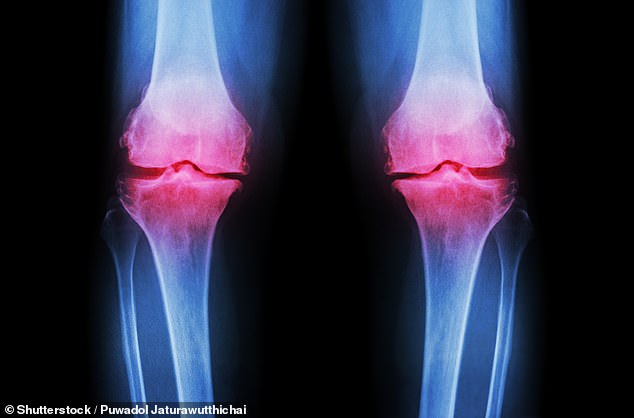

Osteoarthritis occurs when protective cartilage on joints wears down, leading to pain, stiffness, and reduced mobility. While joint damage is a normal part of life, the body typically repairs it. However, excessive stress from high-impact exercise and poor nutrition can overwhelm this natural process. Factors such as genetics, obesity, repeated stress on joints, and injuries all contribute to cartilage degradation. Post-traumatic osteoarthritis, for example, can result from fractures that affect joints, altering their mechanics and accelerating cartilage breakdown.